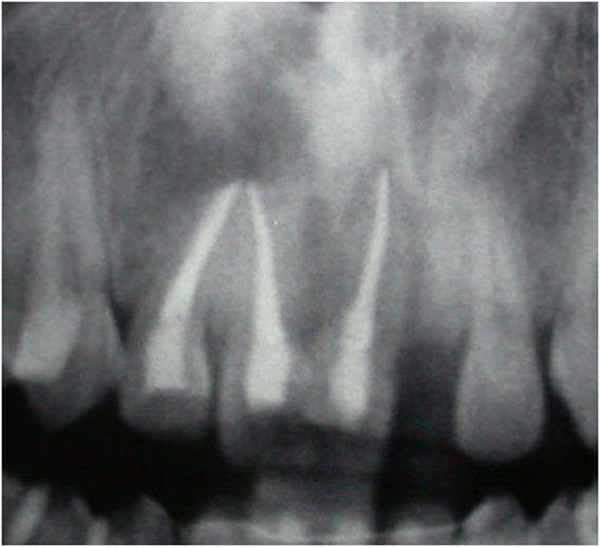

After six months, a radiographic control revealed the persistence of periapical radiolucency (Figure 3). We then decided to perform endodontic surgery, which included exeresis of the lesions (Figure 4), apicoectomy, and retrograde obturation with a reinforced zinc oxide-eugenol cement (SuperEBA).

Figure 3.

Persistence of periapical radiolucency at six months control.